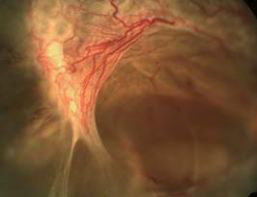

晚期糖网

V期:新(xīn)生血管和增殖膜形成

IV期:新(xīn)生血管為(wèi)區(qū)分(fēn)

VI期:V期+合并有(yǒu)视网膜脱离,可(kě)合并玻璃體(tǐ)积血